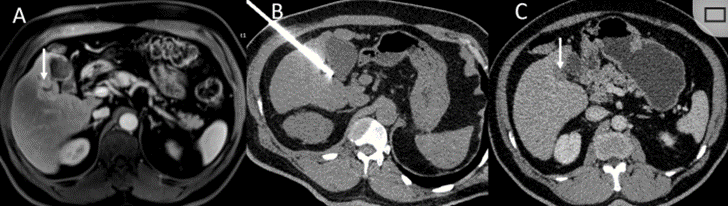

冷凍消融膽囊附近腫瘤病灶

(A)動脈期 MRI 顯示膽囊附近有外周增強病變(箭頭)。

(B)手術過程中 CT 顯示冷凍探針位于病灶內(nèi)。

(C)消融后,術后 1 個月CT 顯示完全消融(箭頭)。